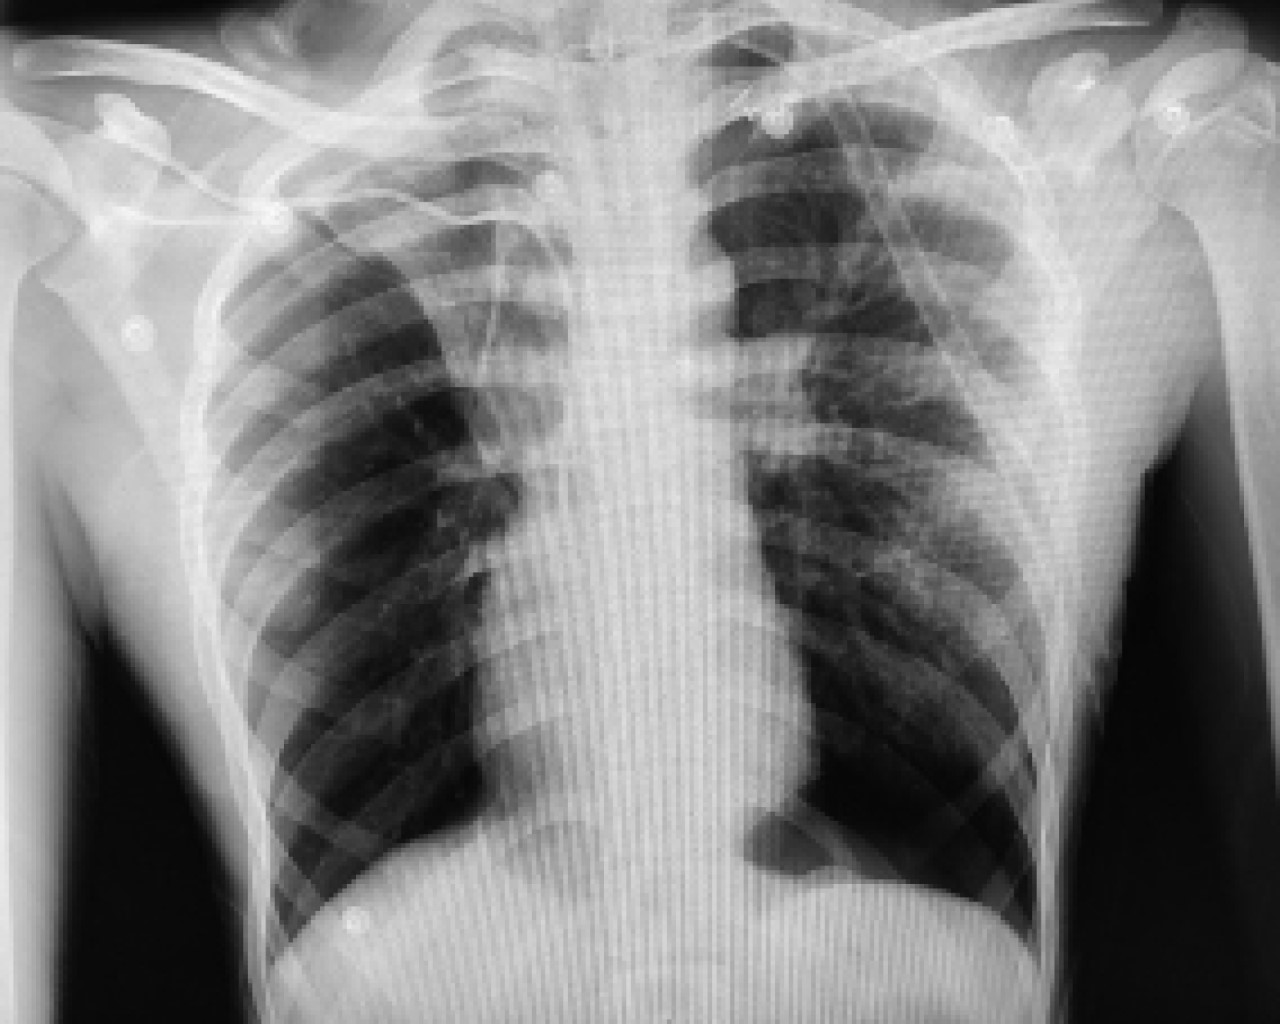

Three weeks later, he came to the emergency department referring a two-day evolution of pain in the left hemithorax, of sudden onset, transfixing, as well as dyspnea at rest; the physical examination revealed hypoventilation of the left hemithorax and hyper resonance to percussion. The X-ray showed recurrent pneumothorax (Figure 1) and an endo pleural probe was placed. Adequate pulmonary expansion was seen on X-ray (Figure 2). Seven days later the patient underwent a seal pleural probe test, presenting dyspnea and chest pain. A control X-ray showed recurrent left pneumothorax (Figure 3), so a CT scan was requested, showing persistent pneumothorax, and left apical bulla, so a surgical protocol for thoracoscopy was initiated.

Figure 1